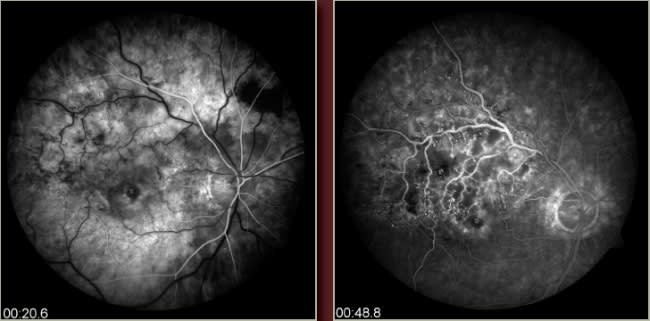

Recent study results show promising treatments for patients who have retinal vein occlusion, which is depicted in these fluorescein angiography images.